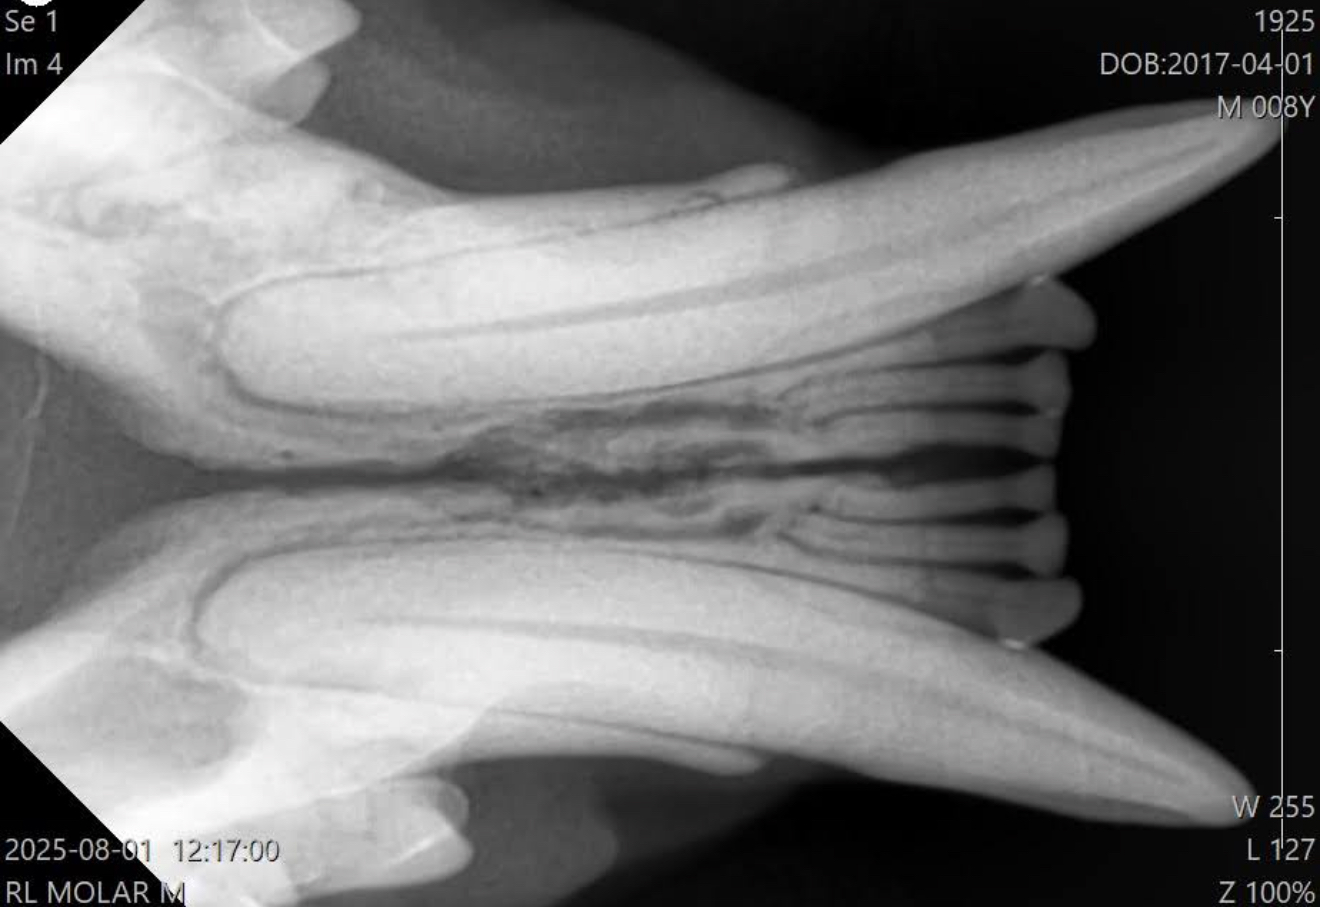

コレが正常な猫の下顎の歯科レントゲン

昨日、一年ぶりに歯科クリーニングand歯科処置をした

14歳の猫ちゃんの下顎は